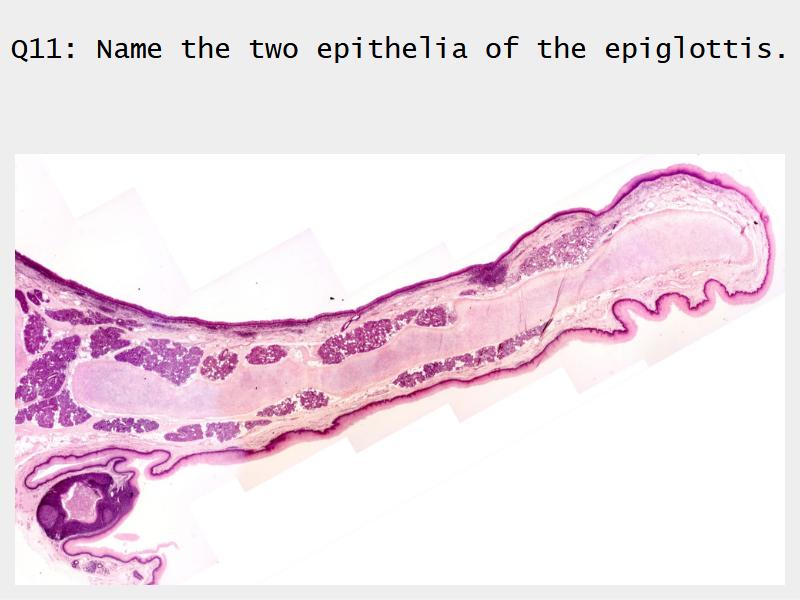

Epiglottis

Respiratory epithelium

- Pseudostratified

- Ciliated

- Columnar

- Epithelium with

- 4 Cells

- Ciliated columnar cells

- Non-ciliated columnar cells

- Goblet cells

- Basal cells